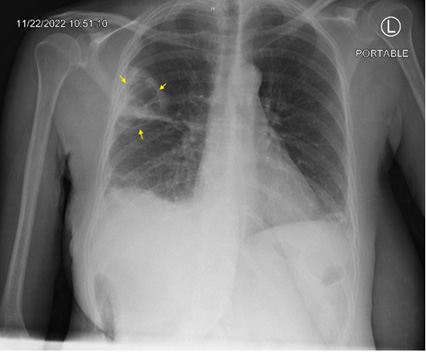

A 53year old woman with a history of alcohol use disorder, COPD, asthma and >20 pack year smoking history presented to the emergency department for two days of worsening shortness of breath and cough with rusty brown sputum and occasional streaks of blood. She denied any fever or chills but endorsed night sweats which she attributed to menopause. On initial evaluation the patient was afebrile, hemodynamically stable and saturating well on room air. Initial work up was positive only for an elevated c-reactive protein of 441. Chest x-ray showed a cavitary lesion in the right upper lobe of the lung measuring 5.7x4.3cm and bibasilar subsegmental atelectasis. Notably, the patient had a chest x-ray 6 months prior that showed no cavitary lesions. The patient was put on oxygen supplementation to assist in resolution of the atelectasis. Subsequent CT chest imaging on the same day showed a 5.1x4.3x5.7 cm thick-walled cavitating lesion in the right upper lobe with right bronchial lymphadenopathy and a small right apical pneumothorax and mild basilar effusion. The patient was put in isolation due to concerns for tuberculosis and further work up was sent including mycobacterial culture along with another infectious workup. Rheumatologic workup was also done secondary to concerns for granulamtosis with polyangitis. She was started on broad coverage with ceftriaxone, doxycycline, and metronidazole (Figures 1-3).

Figure 1: Single view chest X-ray showing thick walled cavitary leision in the right upper lobe 5.7x4.3cm; Yellow Arrows.